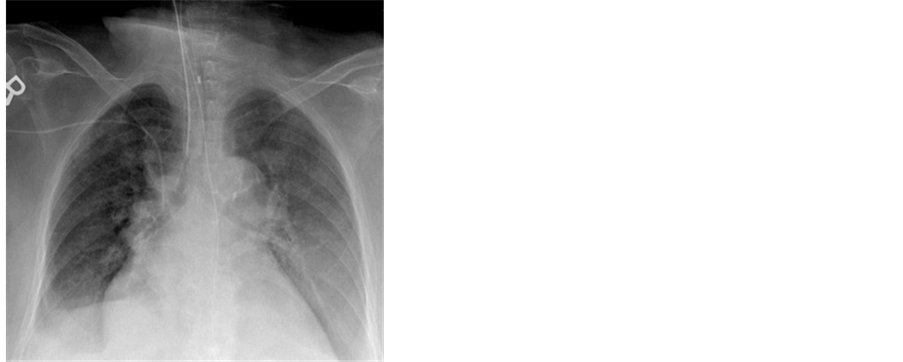

hemorrhage (DAH) was confirmed. Supportive treatment was followed. MRI of the spine showed cement leak through the Para vertebral muscles with no signs of abscess (Figure 4). On day 10, patient was successfully weaned off the ventilator (Figure 5). She was then transferred to the general medical floor where she spent one more week. Her respiratory status continued to improve and she was eventually released home on 1 liter per minute oxygen therapy.

Figure 5. Chest X-ray just before weaning off the ventilator. Clearing previously noted alveolar infiltrates with trachealtube in place.